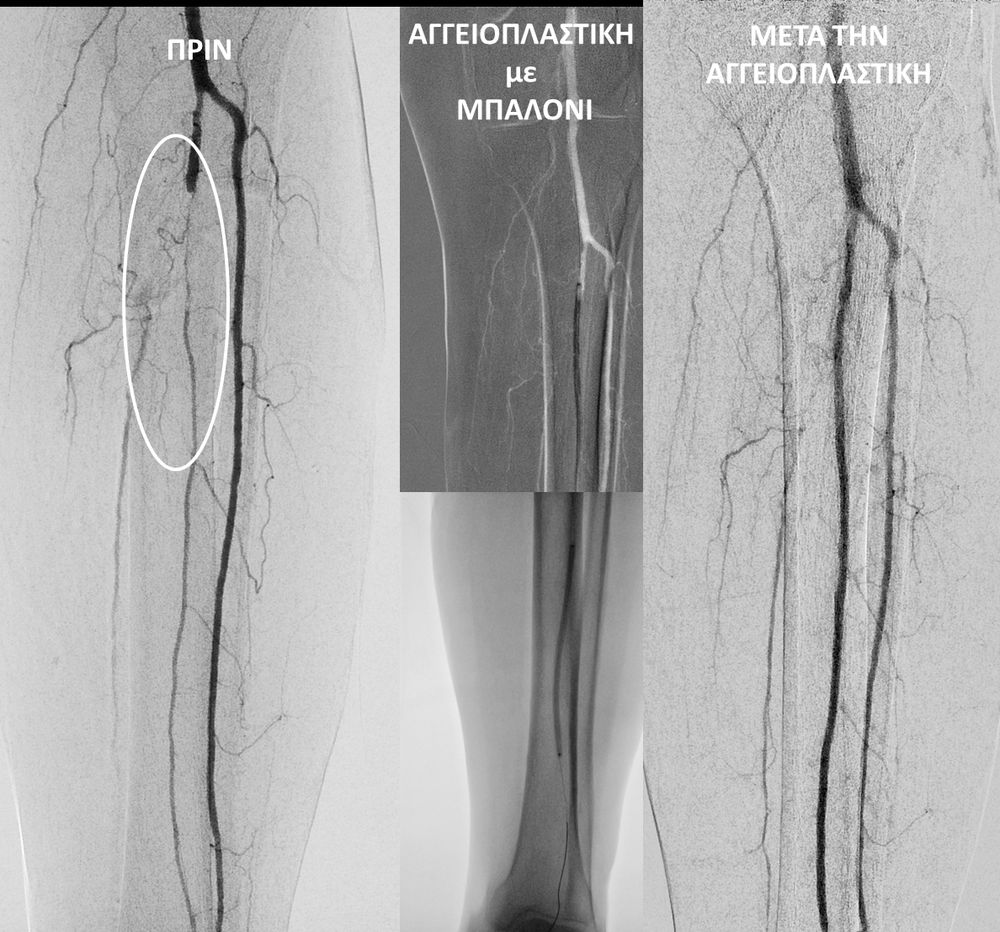

O σακχαρώδης διαβήτης είναι μεταβολική ασθένεια η οποία χαρακτηρίζεται από αύξηση της συγκέντρωσης του σακχάρου στο αίμα (υπεργλυκαιμία) και διαταραχή του μεταβολισμού της γλυκόζης. Ο βαθμός αύξησης της γλυκόζης στο αίμα και η παραμονή των αυξημένων τιμών της για μεγάλο χρονικό διάστημα βλάπτουν, κυρίως, τα μικρά αγγεία, προκαλώντας διαβητική νευροπάθεια, διαβητική νεφροπάθεια, αμφιβληστροειδοπάθεια κ.τ.λ., με σοβαρότατες συνέπειες σε πολλά όργανα-συστήματα.Στην Ελλάδα κάθε χρόνο πραγματοποιούνται 2.000 – 3.000 ακρωτηριασμοί κάτω άκρων, αφού το 4-5% των πασχόντων από διαβήτη εμφανίζει περιφερική αγγειοπάθεια με έλκη ή και γάγγραινα στα πόδια. Σε ποσοστό 80% οι ακρωτηριασμοί θα μπορούσαν να αποφευχθούν και η επεμβατική ακτινολογία μπορεί να βοηθήσει σημαντικά.Η διαδερμική ενδαγγειακή αγγειοπλαστική (percutaneous transluminal angioplasty, PTA) είναι μια ελάχιστα επεμβατική μέθοδος αντιμετώπισης των αρτηριακών στενώσεων ή και αποφράξεων του διαβητικού ποδιού (περιφερικήδιαβητικήαρτηριοπάθεια).